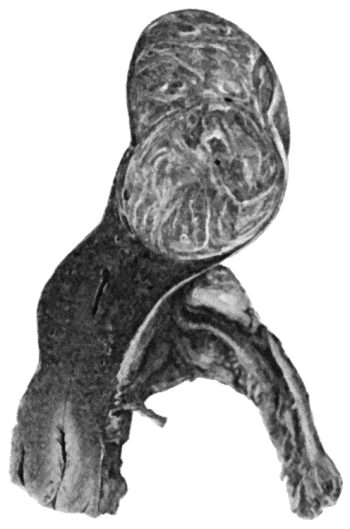

| 133. | Skeleton of Rickety Dwarf | 470 |

| 134. | Changes in the Skull resulting from Ostitis Deformans | 474 |